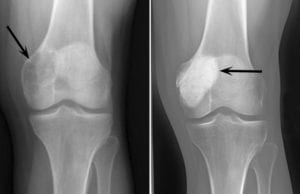

- ساركوما العظام: والساركوما كلمة تعني الورم الخبيث، تُصيب الخلايا العظمية ويظهر علي الاغلب في الركبة او الذراع،

- ويكون في الفئة العمرية ما بين 10 و 19 عاما، وقد يحدث أحياناً عند من هم أكبر من 40 عاماً إذا كانوا يعانون من حالات مرضية أخري